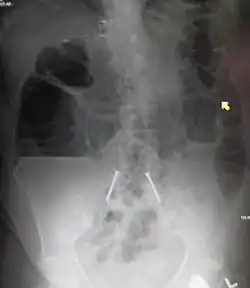

Radiological signs of bowel obstruction include bowel distension (small bowel loops dilated >3 cm) and the presence of multiple (more than 2) air-fluid levels on supine and erect abdominal radiographs.[16] Ultrasounds may be as useful as CT scanning to make the diagnosis.[17]

Contrast enema or small bowel series or CT scan can be used to define the level of obstruction, whether the obstruction is partial or complete, and to help define the cause of the obstruction. The appearance of water-soluble contrast in the cecum on an abdominal radiograph within 24 hours of it being given by mouth predicts resolution of an adhesive small bowel obstruction with sensitivity of 97% and specificity of 96%.[18]